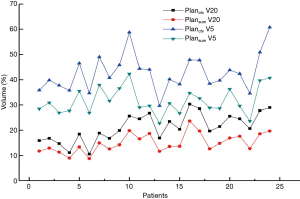

V20 and V5 for Planctv and PlanSum

Planning target volumes (PTVs) on Planctv and PlanSum were obtained by creating a 0.5 cm margin from Vctv and VSum. Targets had both a 100% dose coverage and 95% volume, while the OARs were within standard limits. Our attention was mainly focused on the dose delivered to normal lung tissue, as this not only has a significate effect on normal lung function but can indicate the radiation pneumonia rate. Figure 3 shows V5 and V20 for Planctv and PlanSum. Both V5 and V20 are lower in PlanSum. For Planctv, the mean V5 and V20 is 42.798% and 21.161%, respectively, while that for PlanSum is 31.610% and 14.950%, respectively. The results indicated that the 4D-CT-based plan had an advantage in dosage, with increased tumor tissue dose coverage and a reduction in the complication rate, especially for radiation pneumonia.

The final goal for lung cancer radiation treatment is delivering a high dose of radiation to the target while minimizing the dose delivered to OARs. For radiation treatment of thoracic tumors, the lung tissue inevitably suffers an incidental dosage (23,24), and radiation damage to the lung commonly occurs because this tissue is very sensitive to the X-rays. V20 and V5 mentioned above are very important indexes for estimating lung damage risk (13,25,26). In our work, two plans based on two PTV types (derived from 3D-CTV and 4D-GTV respectively) were used. With a smaller PTV volume, PlanSum has an advantage in protecting lungs and decreasing the rate of radiation pneumonia.

Our study contoured the target volumes in 3D-CT and 4D-CT (CTMip, CTExs and CTSum) images for early stage lung cancer patients to identify any volume differences and target center deviations. Treatment plans based on 3D-CT and 4D-CTSum were compared to quantitatively measure the lung tissue affected by the difference in dosage. For GTV contouring, the 10-phase CTSum was found to be the optimal image for contouring, while volumes contoured in CTMip and. CTExs showed little difference. Considering the workload in contouring in 10-phase CT images, these two types of images can also be used to contour the target. Target centers calculated for the CTMip, CTExs, and CTSum in TPS were very similar. V5 and V20 for 4D-CTSum were both lower than those for 3D-CT, and this can have a significant effect on decreasing radiation pneumonia and protecting the OARs.